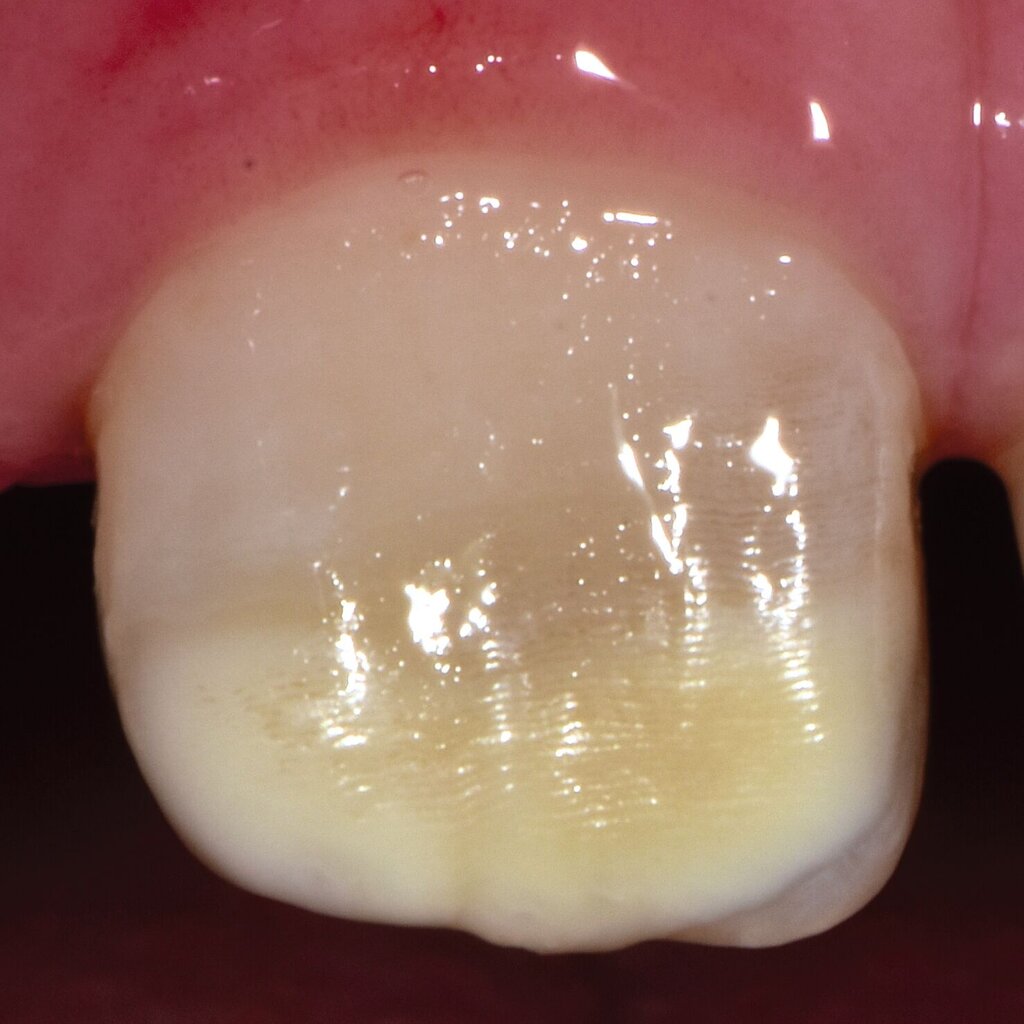

Bei post- beziehungsweise präeruptiven Oberflächendefekten ergibt sich in einigen Fällen die Indikation zur Restauration dieser MIH-Zähne. Unter Verweis auf die Lokalisation von MIH-bedingten Hypomineralisationen außerhalb der typischen Kariesprädilektionsstellen – zum Beispiel okklusale Fissuren und Grübchen oder Approximalflächen – werden diese als „atypische Restaurationen“ (engl.: „atypical restoration“, Abbildung 6) klassifiziert. Als ein weiteres Erkennungsmerkmal gilt die Präsenz von Hypomineralisationen im Bereich der Restaurationsränder. MIH- und kariesbedingte Restaurationen können und sollten sicher voneinander abgegrenzt werden.

Für die Dokumentation und Klassifikation der MIH wurden verschiedene Systeme vorgeschlagen. Als historisch und veraltet gilt der (modifizierte) DDE-Index. Demgegenüber haben die Kriterien der EAPD – abgegrenzte Opazitäten (Abbildung 3 und 4), Schmelzeinbrüche (Abbildung 5), atypische Restaurationen (Abbildung 6) – mittlerweile die weiteste Verbreitung gefunden. Diese wurden 2003 erstmals zur Beschreibung der MIH auf empirischer Basis publiziert [Weerheijm et al., 2003] und den Jahren 2010 und 2022 im Rahmen der damaligen MIH-Workshops bestätigt [Lygidakis et al., 2010; 2022].